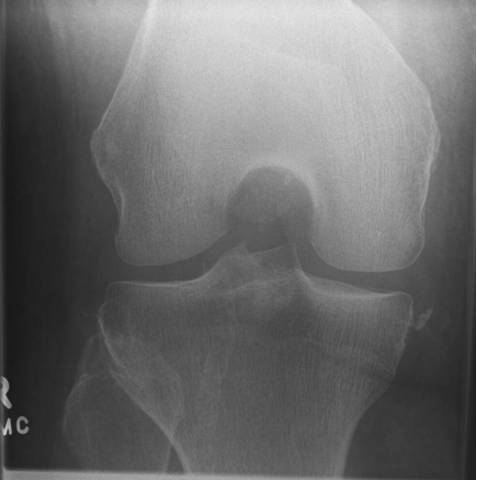

Segond骨折

胫骨平台前外侧撕脱骨折,多因为下肢过度内翻加内旋暴力所致,常伴有前交叉韧带、内外侧半月板的损伤。

反Segond骨折

胫骨平台内侧撕脱骨折,常因为下肢外翻应力加外旋所致。